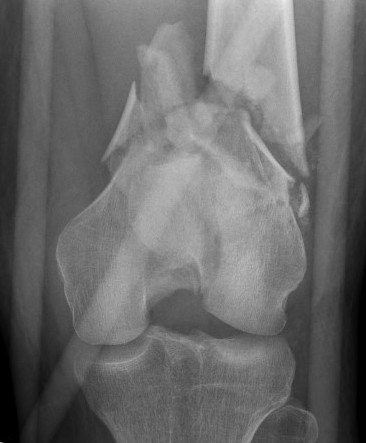

AO Type A: Supracondylar / Extra-condylar

Xray

Options

Lateral plate

Retrograde IM nail

AO Type B1 & B2: Partial articular

Definition

Medial or lateral sagittal split